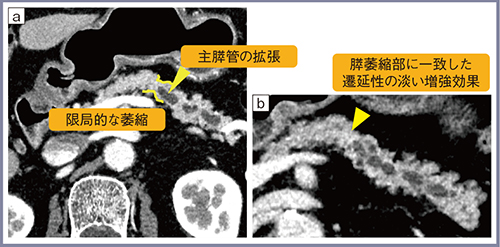

Aquilion Precisionでも腫瘍の指摘が困難な症例もあるが,このような症例においては副次的な所見を確認することが重要である。症例3(60歳代,男性)はCTで指摘困難な微小な膵がん症例で,画像では膵がん自体を指摘することはできないが,膵尾部における主膵管の拡張と,膵尾部の主膵管が途絶している部位に一致して限局的な膵臓の萎縮(くびれ)が確認できる(図3 a)。また,膵尾部の主膵管の途絶部位に一致してごく淡い遷延性の増強効果が認められ(図3 b),このような所見からEUSでの精査を推奨した。EUSでは主膵管の拡張部に乳頭状増殖が認められ,手術の結果,上皮内癌(high grade PanIN)と診断された。

このように,膵がんを視認できない場合にも,早期膵がんを示唆する所見をいかに発見するかが重要となる。

図3 症例3:60歳代,男性,CTでの指摘困難例